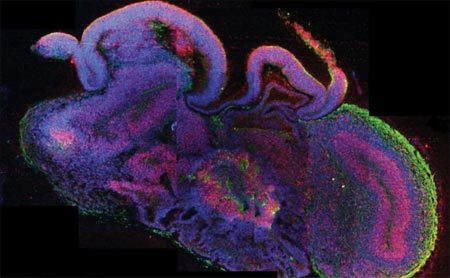

Bộ não non nớt tí hon ra đời từ các tế bào gốc trích lấy từ da người. Ảnh: National News |

Các bộ não mô phỏng mới có kích thước chỉ đạt 3 - 4 milimet chiều ngang và có cấu trúc tương tự như bộ não người còn non nớt. Chúng đã giúp nhóm nghiên cứu nhận diện khiếm khuyết ảnh hưởng tới sự phát triển bình thường của bộ não người ở bệnh nhỏ đầu.